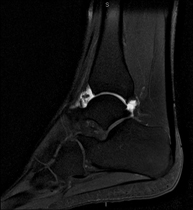

Artro-RM de TurmellExploració per a l'estudi de les lesions en petites estructures anatòmiques de l'articulació que solen produir-se en pacients que pateixen luxació o inestabilitat crònica. L'estudi ve precedit per una injecció de contrast a l'interior de l'articulació, realitzada sota control de raigs X. La durada total dels dos procediments és de 50 minuts.